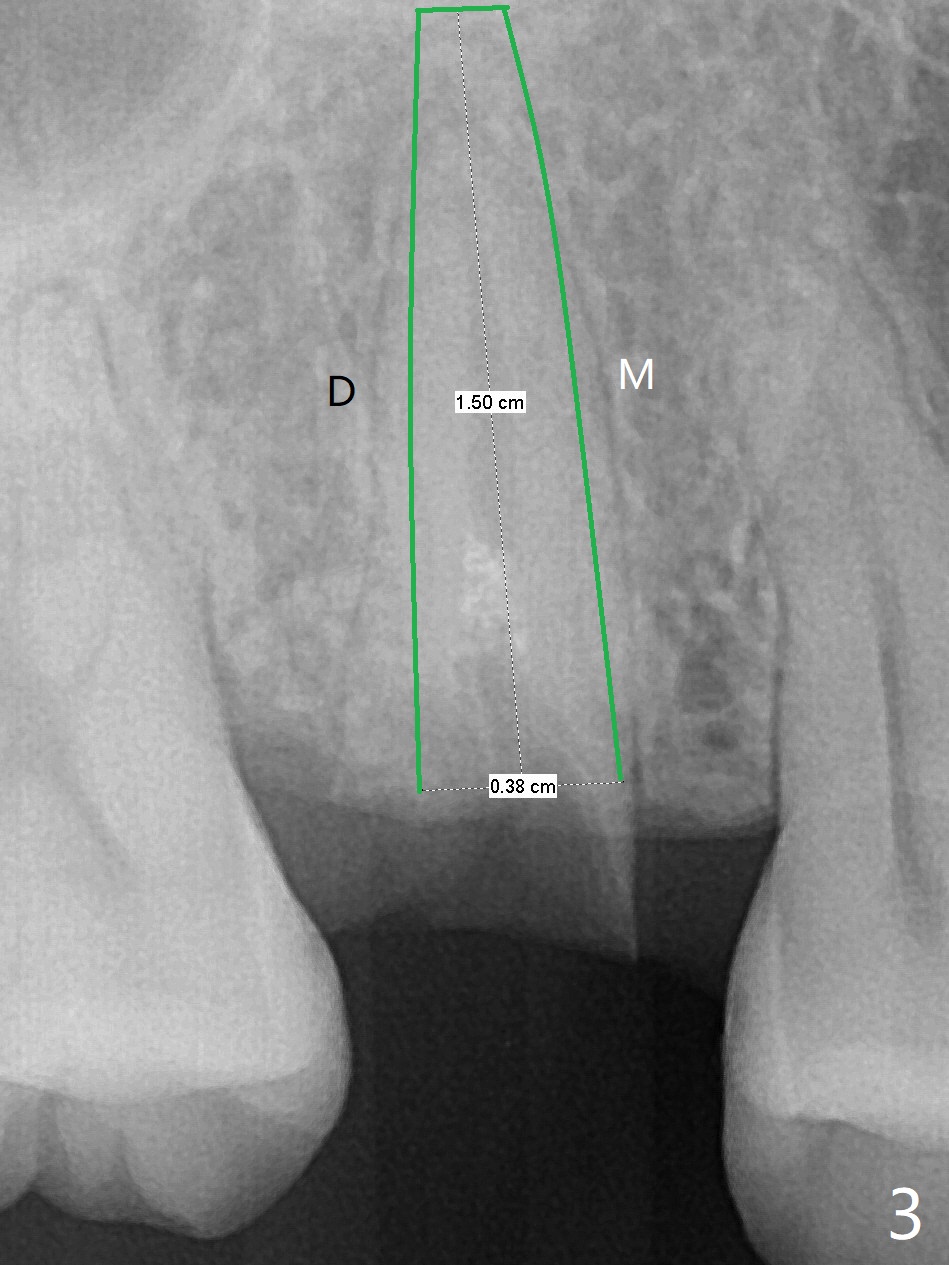

A 29-year-old woman requests implant for the residual root of the tooth #4 after initial RCT in home country (Fig.1,2 (S: sinus)). It appears that a 15 or 16 mm long implant should be placed to engage into the apical native bone and sinus floor (*) for stability (Fig.3,4). Further stability is obtained by contact with the mesial (M), distal (D) wall or both.